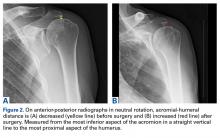

For all SCR patients, preoperative and postoperative radiographs were obtained in 2 planes: anterior-posterior with arm in neutral rotation, and scapular Y. On anteroposterior radiographs, AHD was measured from the most proximal aspect of the humeral head in a vertical line to the most inferior portion of the acromion ( Figures 2A, 2B ).

Mean age at time of surgery was 61.33 years (range, 47-78 years). Of the 8 surgeries, 7 were performed on the dominant arm. Mean number of previous rotator cuff surgeries was 1.50 (SD, 0.93; range, 0-3). Mean follow-up was 32.38 months (range, 25-39 months). For 1 patient, who lived out of state, a postoperative radiograph, a 2-year ASES score, and a 2-year VAS pain score were obtained, but postoperative US could not be arranged. From before surgery to 2 years after surgery, mean ASES score improved significantly ( P < .00002), from 41.75 (SD, 12.71; range, 25-58) to 86.50 (SD, 12.66; range, 63-100) ( Figure 3 ), and mean VAS pain score decreased significantly ( P < .00002), from 6.25 (SD, 1.56; range, 4-8.5) to 0.38 (SD, 1.06; range, 0-3) ( Figure 4 ). The historical control patients’ mean (SD) postoperative VAS pain score, 3.00 (3.37), was significantly ( P < .05) higher than that of the study patients, 0.38 (1.06). However, there was no significant difference in the 2 groups’ mean (SD) ASES scores: historical control patients, 70.71 (29.09), and study patients, 86.50 (12.66).AHD was measured on a standard anteroposterior radiograph in neutral rotation. The Hamada grading scale16 was used to classify the massive RCTs before and after surgery. Before surgery, 4 were grade 4A, 1 grade 3, 2 grade 2, and 1 grade 1; immediately after surgery, all were grade 1 (AHD, ≥6 mm). Two years after surgery, 1 patient had an AHD of 4.6 mm after a failure caused by a fall. Mean (SD) preoperative AHD was 4.50 (2.25) mm (range, 1.7-7.9 mm). Radiographs obtained immediately (mean, 1.22 months; range, 1 day-2.73 months) after surgery showed AHD was significantly ( P < .0008) increased (mean, 8.48 mm; SD, 1.25 mm; range, 6.0-10.0 mm) ( Figure 5 ).

The case of the out-of-state patient with only an immediate postoperative (day after surgery) radiograph was included only in the immediate postoperative AHD data. As of this writing, radiographs were most recently obtained at a mean (SD) follow-up of 27.24 (4.37) months (range, 24.03-36.57 months). Mean (SD) postoperative AHD was 7.70 (2.08) mm (range, 4.6-11.0 mm), which was significantly ( P < .05) larger than the preoperative AHD. There was no significant difference between the immediate postoperative and the 2-year postoperative AHD measurements (Figure 5).Mean graft size was 2.9 mm medial × 3.6 mm lateral × 5.4 mm anterior × 5.4 mm posterior. Three patients had AMC performed. There was a significant ( P < .05) difference in ASES scores between patients who had AMC performed (93) and those who did not (77).